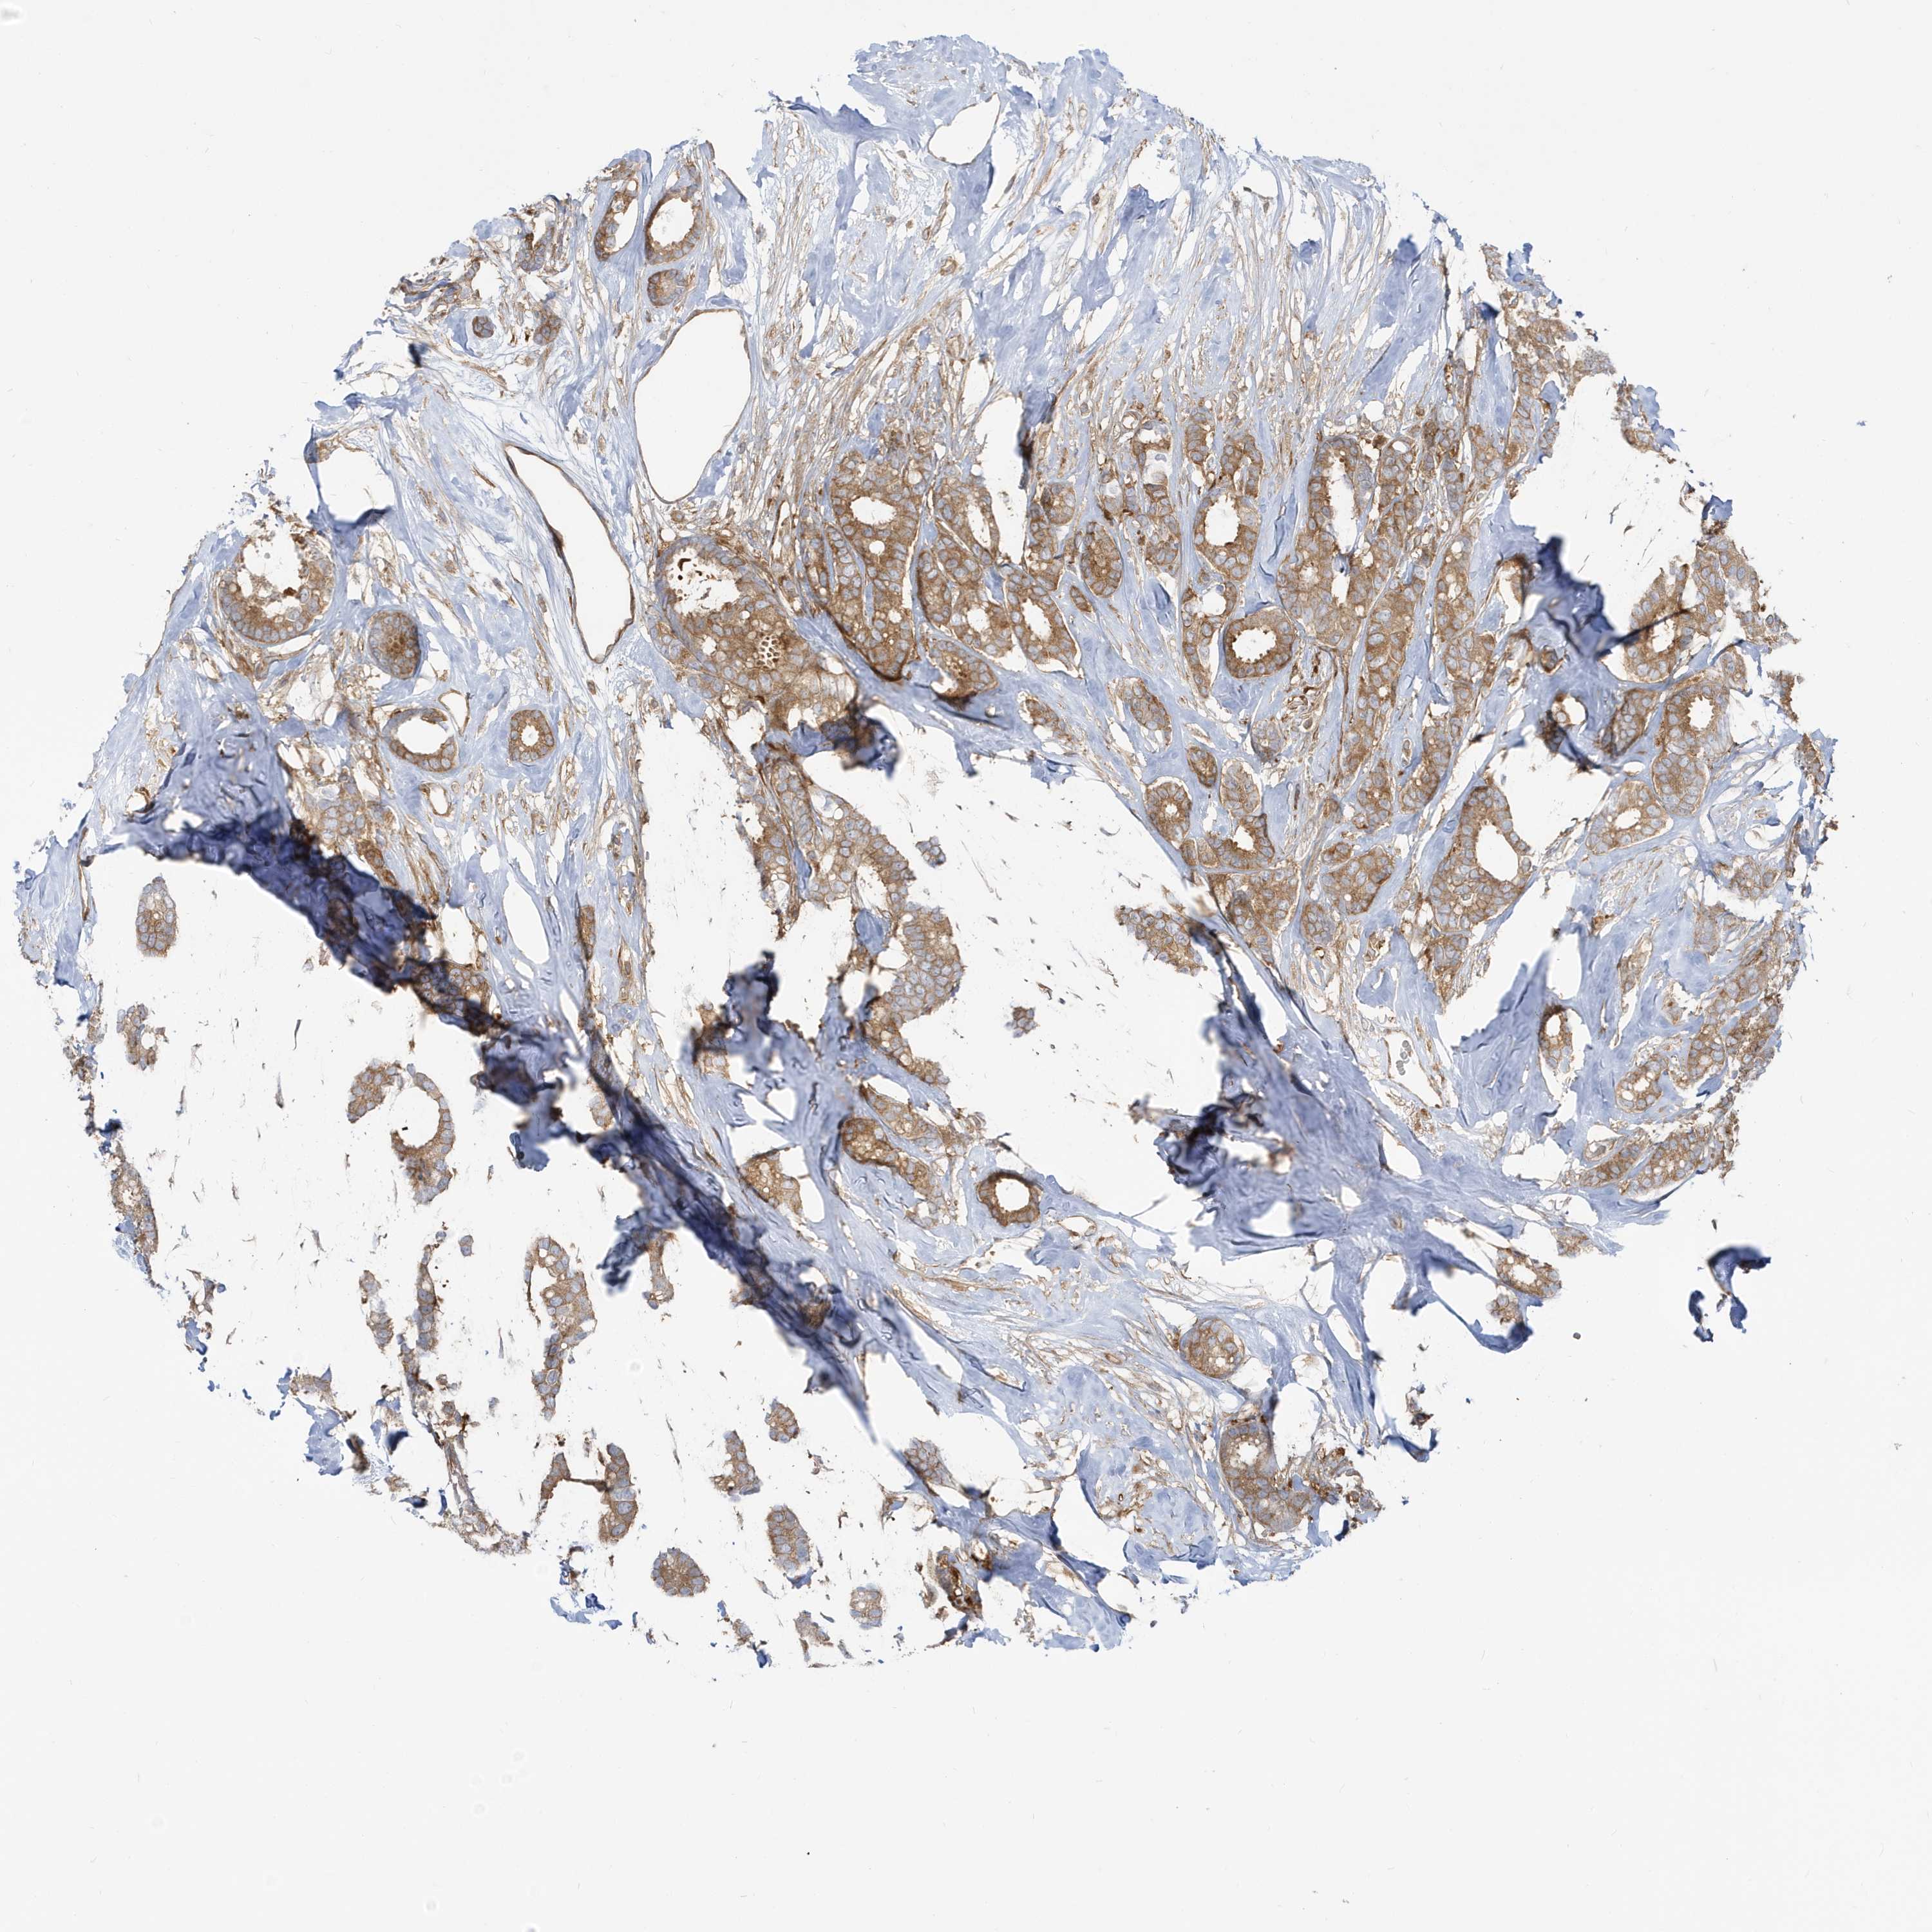

CANCER BREAST CANCER Show tissue menu

BRCA TCGA BRCA VALIDATION PROTEIN EXPRESSION